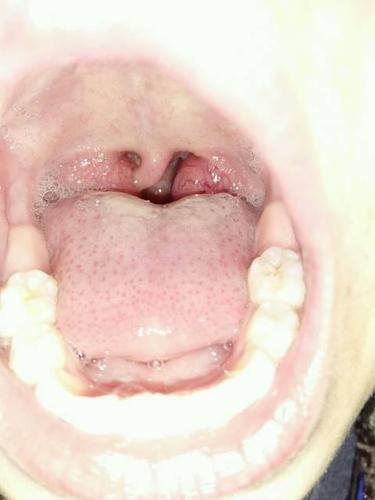

正常扁桃体照片,扁桃体正常大小图片

正常扁桃体以及肿大的扁桃体

在调理1个月后 扁桃体成功缩小到下图这样

扁桃体正常大小图片

扁桃体正常的图片真人

健康扁桃体图片

正常扁桃体是什么样的

正常儿童扁桃体照片

正常人的扁桃体实拍图

正常扁桃体图片实拍

健康扁桃体高清图片

正常扁桃体图片

扁桃体图片正常的图片

正常扁桃体

正常人扁桃体

正常扁桃体图片真实

正常扁桃体图片真人